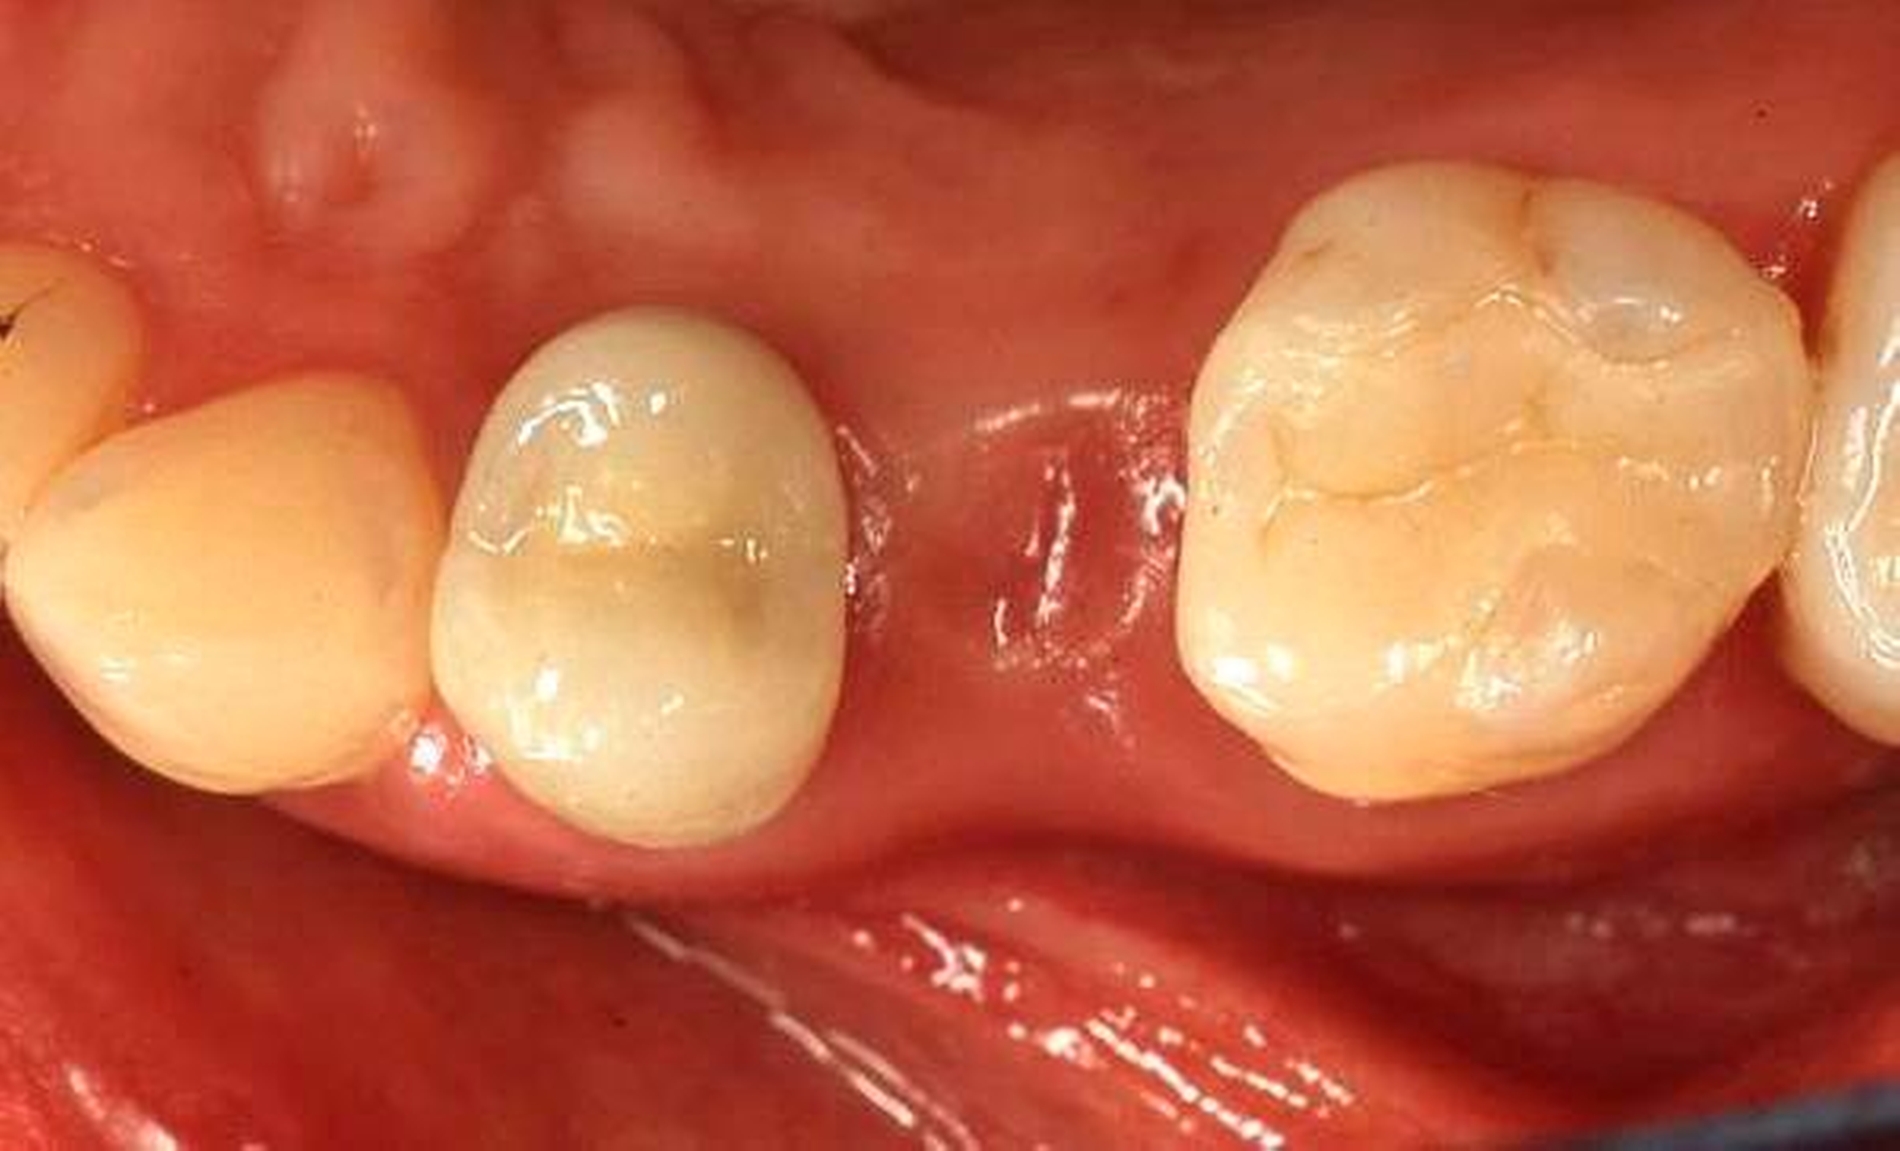

Abbildung 2: Direkte Teilüberkronung im Seitenzahnbereich (R1-Technik)

In den Abbildungen 1 bis 3 werden Optionen für frugale Interventionen auf restaurativem Sektor aufgeführt. Es handelt sich um direkte Vollüberkronungen im Frontzahnbereich (hier: hergestellt in R1-Technik / einphasig) (Abbildung 1), direkte Teilüberkronungen im Seitenzahnbereich (hier: hergestellt in R1-Technik / einphasig) (Abbildung 2), Reparatur-Restaurationen im Seitenzahnbereich (hier: hergestellt in R2-Technik / zweiphasig) (Abbildung 3). Technische Einzelheiten zur Vorgehensweise und den Ergebnissen sind an anderer Stelle beschrieben (Literatur siehe oben).

Für die in Abbildung 2 dargestellte Situation eines tief zerstörten Prämolaren gelten ähnliche Charakteristika. Es gibt in der restaurativen Zahnheilkunde viele Neuerungen, die das Behandlungsspektrum vergrößert haben. Dazu zählen unter anderem:

ein- oder zweiphasiges Vorgehen je nach Defektausdehnungen (R1- und R2-Technik),

von Präparationsgrenzen unabhängige Verschalungstechniken, die auch bei nicht-kariesbedingten Zahnhartsubstanzschäden (wie etwa Hypomineralisationen) zum Einsatz kommen können,

schadensgerechte Reparaturtechniken (Abbildung 3),

neuartige Insertionstechniken, die unter anderem die Anpassung neuer Restaurationen an vorhandene prothetische Versorgungen (Reziproktechnik) erlauben.